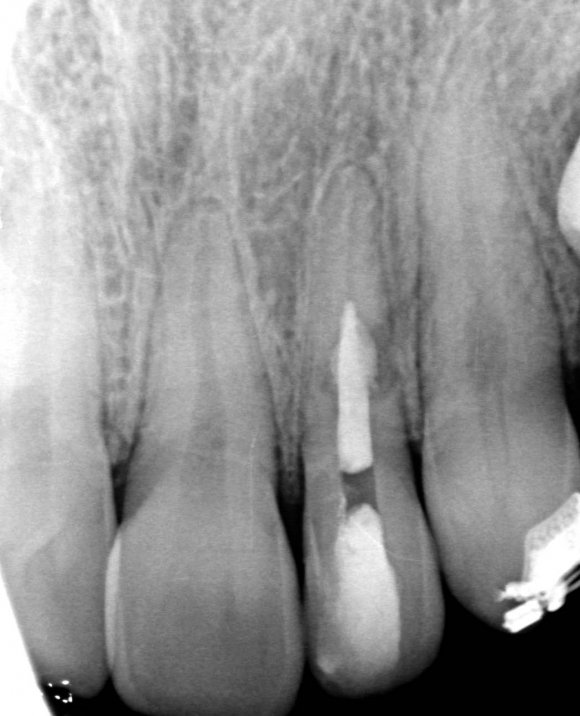

The X-ray snapshots showed signs of internal resorption in tooth 2.2.

The CBCT revealed intraroot perforating resorption on the vestibular root surface. In addition, a possible cause of resorption was identified as Oehlers' Type I invagination (1957), which was based on the radiological findings. According to the classification, Type I invagination is covered with enamel and is located within the coronal part, extending no further than the enamel-dentin junction. The authors believe that the infected invagination zone with subsequent creeping infection of the root pulp brought about the resorption. The response to the cold stimulus was very insignificant, especially in comparison with tooth 12. This made it clear that an irreversible destructive process is going on in the damaged tooth. Since the patient was planning orthodontic treatment and the resorption process could grow worse, it was decided to conduct endodontic treatment.

The diagnosis presented some difficulties and it was necessary to discriminate between internal and external resorption, as they require dififerent treatment tactics. While external resorption provides for either observation or surgery, depending on the extent of the defect and location, internal resorption often implies endodontic treatment.

The radiographic findings were very similar to external resorption, but some moments were not typical of it.

In favor of external resorption was the shape of the defect, with the wider defect facing the bone, the shape of the defect was not rounded, which would be characteristic of internal resorption.

Also, there were signs in favor of internal resorption. The defect was below the cervical part, which is not typical of external cervical resorption. The response to cold stimuli reduced, which is not characteristic of external resorption, as it affects the pulp only in the last stages of tooth structures decay. Furthermore, the X-ray obliteration of the root canal beyond the resorption area is not characteristic of external resorption. Visit 1: Pre-op X-ray plus anesthesia with sol. Ubisthesini 4% -1 ml, isolation with rubberdam. The access was made as close as possible to the incisal edge. When opened, at first glance the pulp chamber looked quite II.